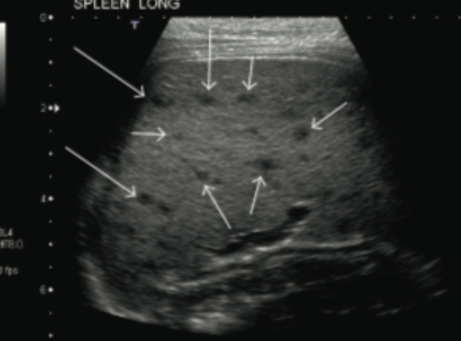

B. henselae can act like M. tuberculosis and involve many organs: liver, spleen >> others (SNC, eye, bones, heart, and many others) - like in this case.

Disseminated CSD treatment: rifampin + azithromycin